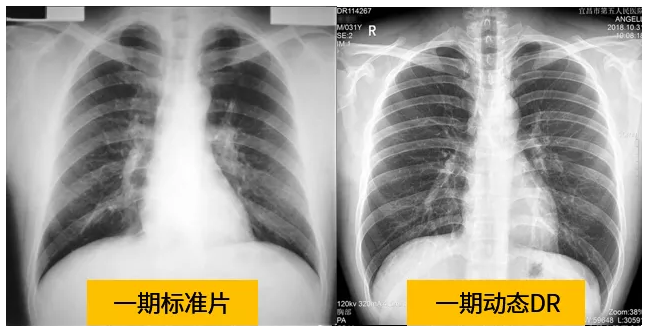

動態dr的拍攝效果圖

動態DR技術與普通DR單截面診斷的不同就是在操作過程中,可以隨時切換成透視模式,透視/攝片模式實時切換,對陰影進行多角度動態的鑒別。實時點片、實時回放、連續點片等多功能大大的增加了初診的準確率。在小陰影的形態和性質,特別是不規則小陰影的判斷方面提升,從而達到提高胸片整體判斷準確性。

根據數據統計表現,利用動態dr進行檢查的話,圖像的質量和輻射劑量相對較少。并且動態DR在圖像清晰度和射線穿透力方面完全能達到塵肺診斷的要求。這種檢查效果的精準和便捷性是和普通設備不一樣的,動態DR塵肺攝影應用于塵肺疾病診斷中,可以提高檢出率及優片率。